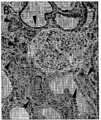

도 7은 세뇨관-농축된 B2와 세뇨관 세포-고갈된 B4 아분획물 (subfraction) 간의 마커 발현에 대한 비교 분석을 나타낸다.

7 shows a comparative analysis of marker expression between tubule-enriched B2 and tubular cell-depleted B4 subfractions.